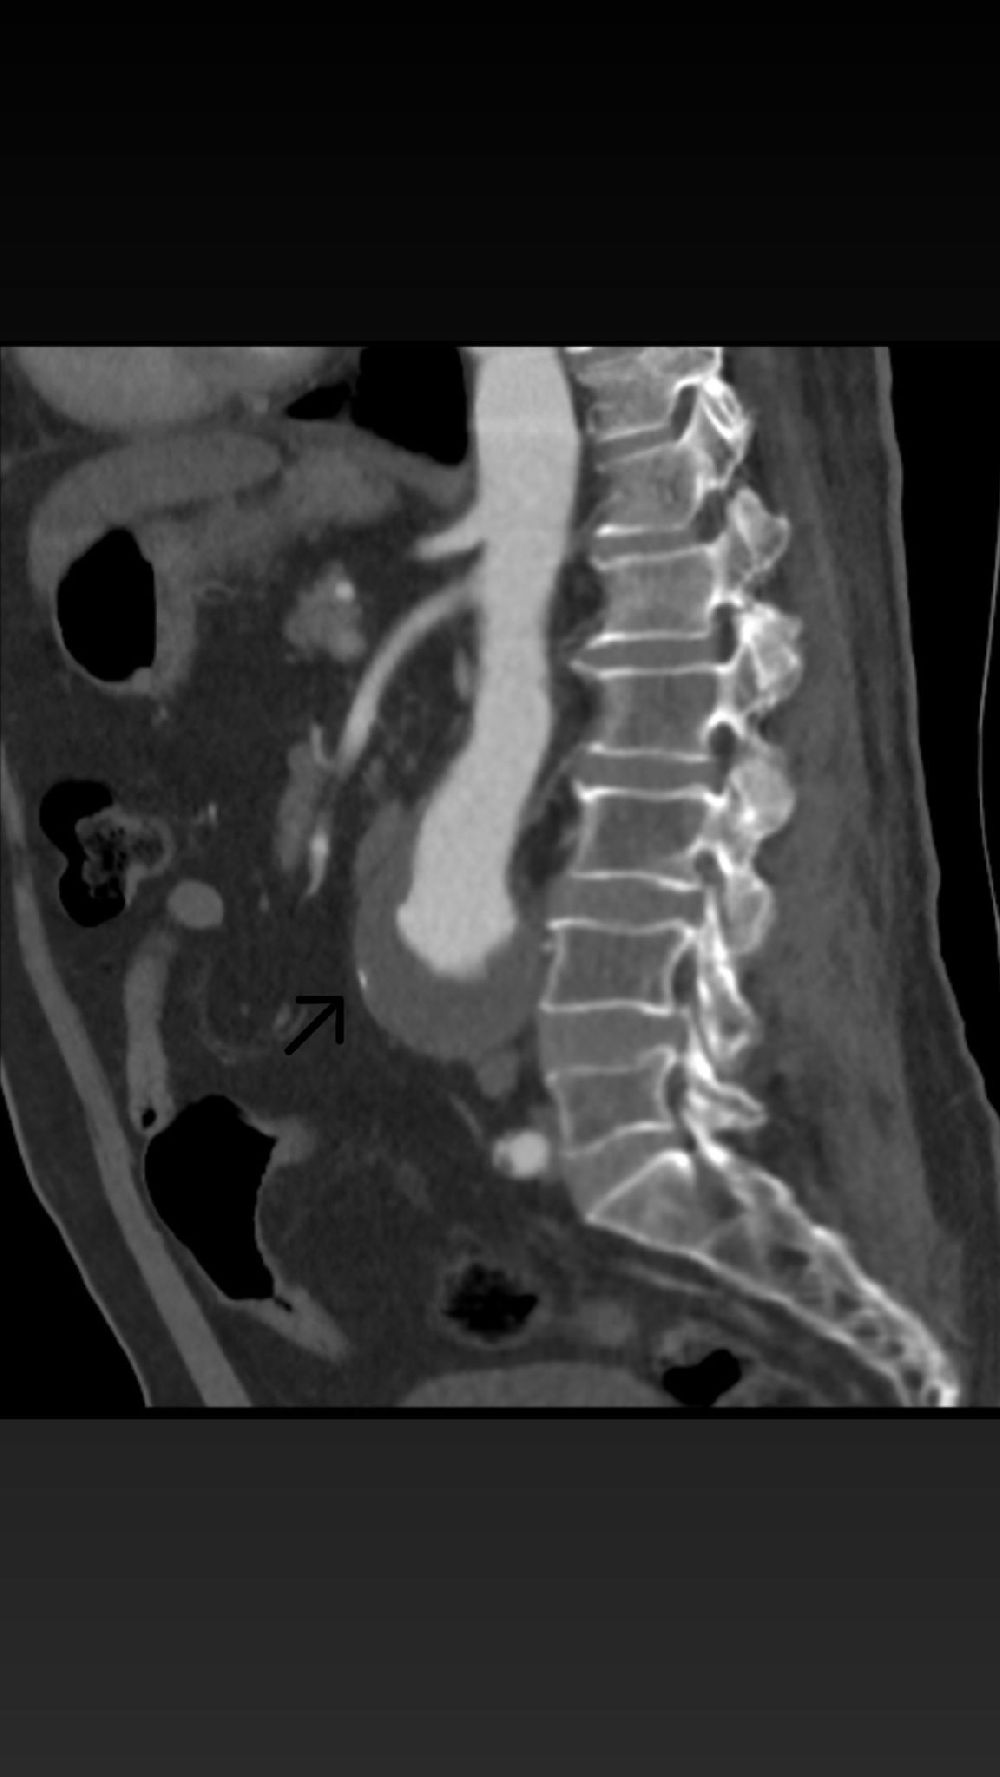

Karın aort anevrizması, vücudun en büyük atardamarı olan aortun karın bölgesindeki genişlemesiyle ortaya çıkan, ciddi ve hayati risk taşıyan bir hastalıktır. Kontrol altına alınmadığında damarın yırtılmasına (rüptür) neden olabilen bu durum, erken müdahale gerektiren kritik bir sağlık sorunudur. 68 yaşındaki hastanın yapılan tetkiklerinde, aort damarında 56 mm’ye ulaşan bir genişleme tespit edildi ve bu yüksek riskli tablo karşısında EVAR prosedürü uygulanmasına karar verildi.

Operasyon, kasık bölgesinden yapılan küçük kesiler aracılığıyla minimal invaziv şekilde gerçekleştirildi. Genişleyen damar bölgesine özel bir greft kaplı stent yerleştirilerek anevrizmanın bulunduğu bölge izole edildi ve damarın normal akışı sağlandı. Bu yöntem sayesinde hastanın iyileşme süresi de açık cerrahiye göre daha hızlı ve konforlu hale geldi.